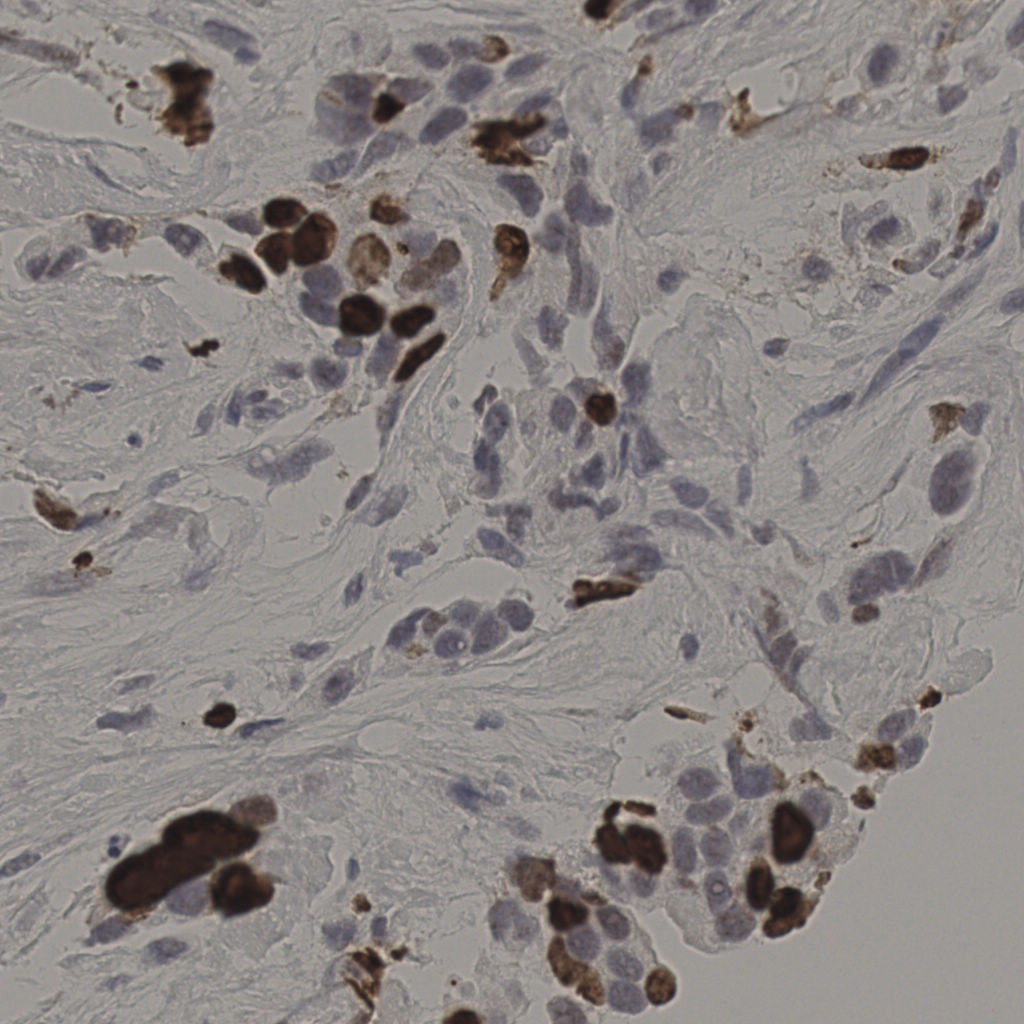

17.75%

Ki67 指数

阴 7986 阳 1723